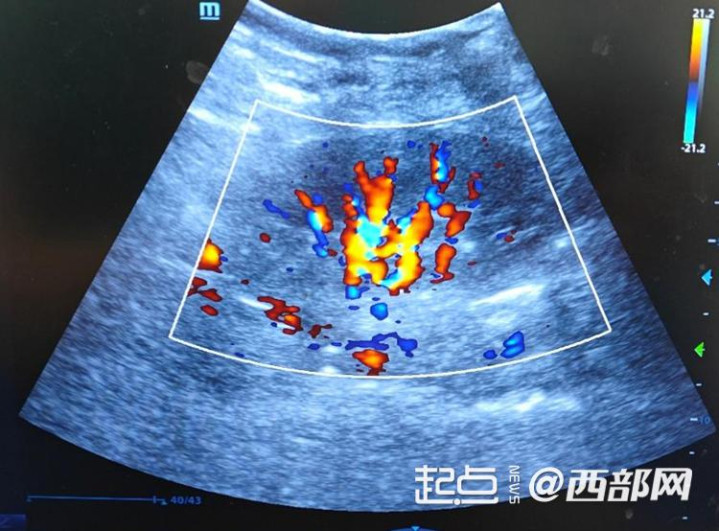

移植肾血流超声

经过严谨的术前评估、成全的准备以及高效的伦理审批经过,手术定期开展。术中,西京病院泌尿外科肾移植团队凭借丰富的临床西席和深通的技艺,精确完成血管吻合等要津操作,通盘过程告成通顺,pk10怒放血流后移植肾即刻复原功能并产生尿液。